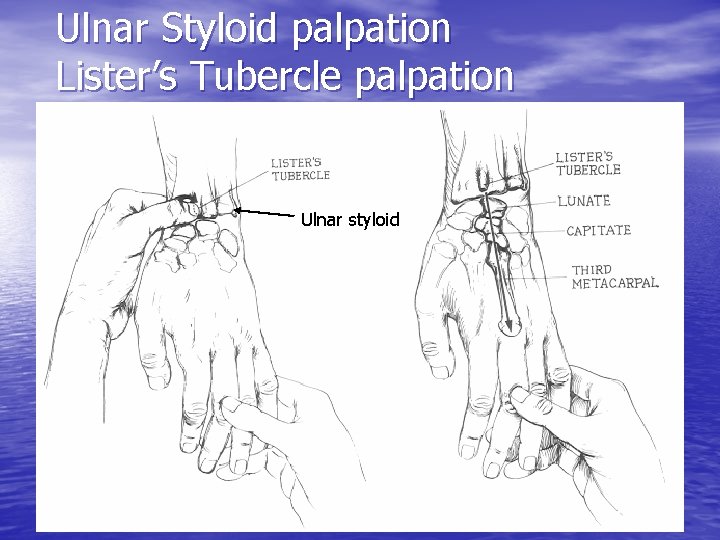

Ulnar Styloid palpation Lister’s Tubercle palpation Ulnar styloid